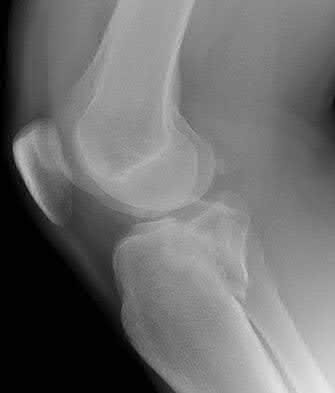

1. # A 32-year-old male sustains the injury shown in Figure A and undergoes treatment as shown in Figure B. Following placement of this implant, what is the best technique to confirm it is not too proud proximally?

1. Lateral radiograph of the knee

The safe zone for tibial nail placement as seen on radiographs is just medial to the lateral tibial spine on the anteroposterior radiograph and immediately adjacent and anterior to the articular surface as visualized on the lateral radiograph.

Tornetta et al specifically located the safe zone for nail entry in a study using fresh frozen cadaver knees. The authors found that the safe zone for nail placement is located 9.1+/-5 millimeters lateral to the midline of the plateau and three millimeters lateral to the center of the tibial tubercle. The width of the safe zone averaged 22.9 millimeters and was as narrow as 12.6 millimeters.

The starting point of the of the nail can be best viewed on the lateral knee radiograph, an example of which is shown in Illustration A. Illustration B shows the "sweet spot" for nail insertion as defined by Tornetta.